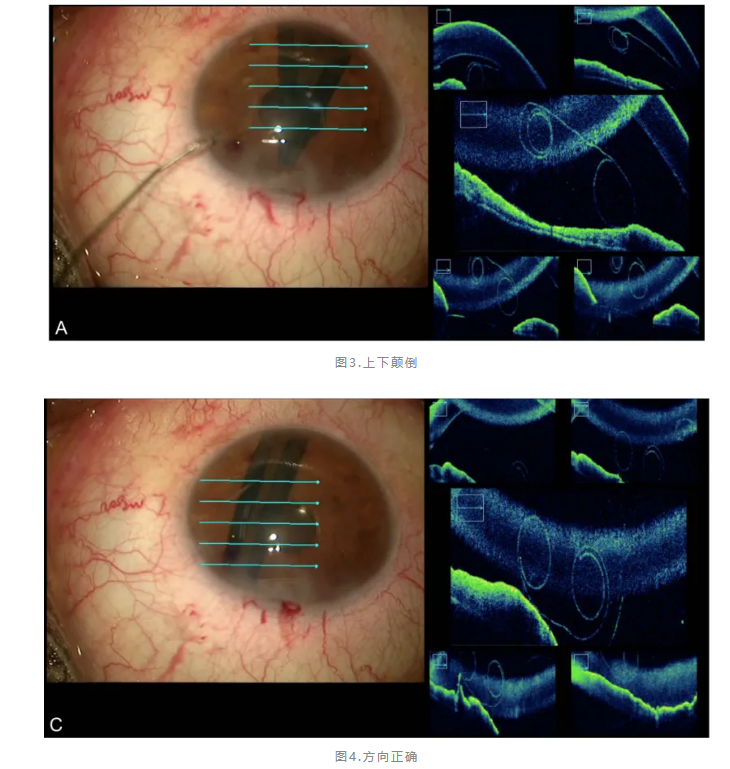

方法三:术中OCT

法国巴黎团队将光谱域OCT直接集成在手术显微镜中,为植片方向识别提供了革命性解决方案[4]。该系统能够通过5μm轴向分辨率的高清OCT图像实时评估植片方向,即使在严重角膜水肿影响直接观察的情况下也能准确判断。研究显示,14例连续病例均成功识别植片方向,平均展开时间仅6.1分钟,相比传统方法显著缩短。该技术不仅避免了额外的植片操作,减少内皮细胞损伤,还能扩大DMEK手术适应证至严重水肿病例。